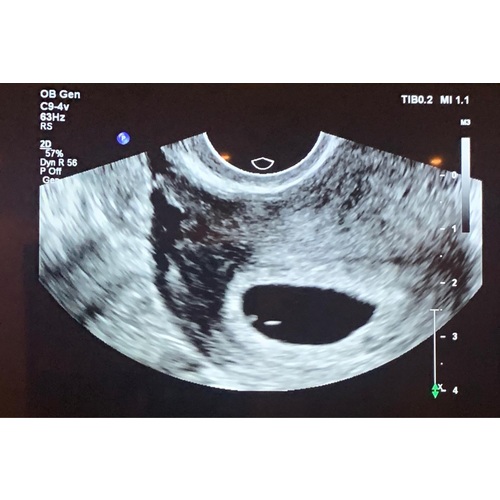

Hi, wow ik maak nu precies hetzelfde mee. Laatste menstruatie begon op 15 september. Vandaag onze eerste echo en het vruchtzakje was leeg.

Dit was onze echo gisteren. Zouden 8 weken zijn volgens berekening. Maar vk ...

Hoihoi, ik had donderdag een afspraak in het zkh. Daar zagen we op de echo een ‘rondje’ en iets wat op een vruchtje leek. De arts kon nog niet met 100% zekerheid zeggen welke kant het op zou gaan. Besloten om een week af te wachten en als we aankomende donderdag geen verandering zien dan beginnen met de medicatie.

Hoi Lisa, ik begrijp precies wat het allemaal met je doet. Eerste week werd ik ook psychisch niet goed van. zelfs ging ik heftig reageren op collega’s! Artsen willen voor de zekerheid nog een weekje wachten omdat je pas een weekje hebt gewacht. Ondertussen groeit wel de placenta. en als je een regelmatige cyclus hebt, en als je zeker weet dat je nooit langer dan naast gemiddelde 14 dagen eisprong na de eerste dag van je laatste menstruatie 1 of 2 weken late eisprong kan hebben, horen ze echtwel meer te zien met 9 weken. Op internet zie je genoeg echo’s hoe t met 9 weken eruit moet zien.